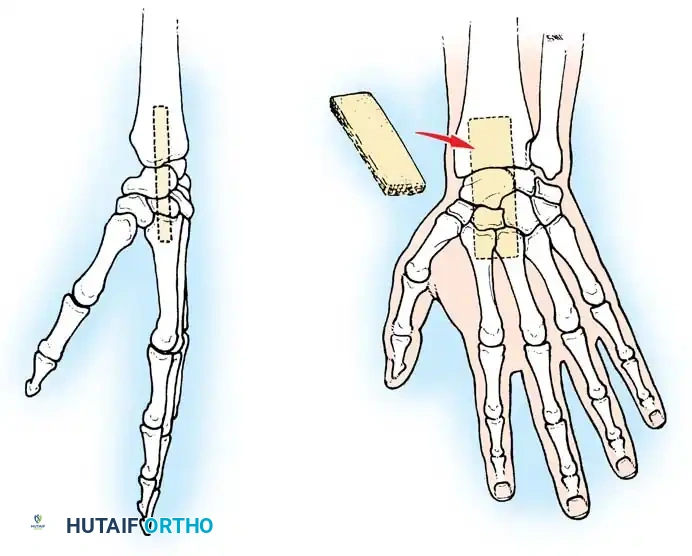

Surgical Technique for Ulnar Shortening Osteotomy:

1. Approach: A longitudinal incision is made over the subcutaneous border of the distal ulna. The interval between the ECU and flexor carpi ulnaris (FCU) is utilized.

2. Plate Application: A specialized ulnar shortening osteotomy plate is applied to the volar or tension surface of the ulna.

3. Osteotomy: A precise oblique or step-cut osteotomy is performed using a cutting guide. The amount of bone resected (typically 2 to 4 mm) is calculated preoperatively based on the degree of positive variance.

Application of a specialized cutting guide to perform a precise, parallel oblique osteotomy of the ulnar diaphysis.

- Compression and Fixation: The osteotomy site is reduced and dynamically compressed using the plate's compression device or an articulated tension device.

The osteotomy is closed and rigidly compressed using a dynamic compression plate, ensuring primary bone healing and immediate structural stability.

- Closure: The periosteum and soft tissues are meticulously closed over the plate to minimize tendon irritation.